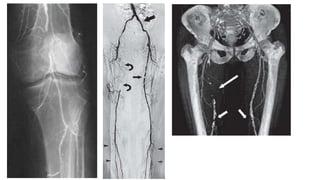

• Angiography (conventional, DSA, CT or MR Angiography)

Investigation • General bloodtests • RBS, HbA1c, urine sugar, UEC, Lipid levels, HIV test, CRP, ASA, Rh • Cardiac assessment • CXR, ECG, echo • Specific limb/vascular exam • Doppler (with quantitative ABPI) • Duplex scan • Angiography (conventional, DSA, CT or MR Angiography)